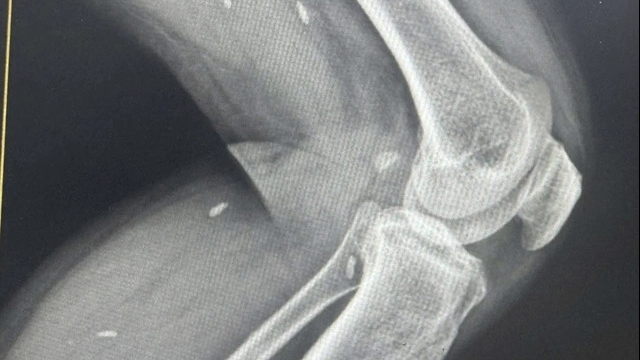

CLB Anh em Đà Nẵng hiện thu hút sự tham gia của nhiều bạn trẻ đến từ các ngành nghề, độ tuổi khác nhau. Có nhiều bạn đang là sinh viên nhưng sẵn sàng tham gia vào các hoạt động nhân văn của CLB, lan tỏa những thông điệp ý nghĩa. Điểm chung giữa họ là có tấm lòng yêu thương, nhân ái. Trong 15 chương trình đã được thực hiện thành công, điểm đến của CLB là Bệnh viện Đa khoa miền núi phía Bắc Quảng Nam (đóng tại H. Đại Lộc) và Bệnh viện Chỉnh hình và Phục hồi chức năng Đà Nẵng.

Bà Hồ Thị Hoa (trú Quảng Ngãi) nằm điều trị tại Bệnh viện Chỉnh hình và Phục hồi chức năng Đà Nẵng cầm trên tay suất cơm nóng hổi mà không giấu được niềm xúc động. Bà Hoa cho hay, hoàn cảnh gia đình khó khăn nên để có thể nằm điều trị lâu dài bà phải chắt chiu từng đồng, việc ăn uống cũng phải tiết kiệm. Vì thế, với những suất ăn miễn phí nhận được, bà mừng lắm.